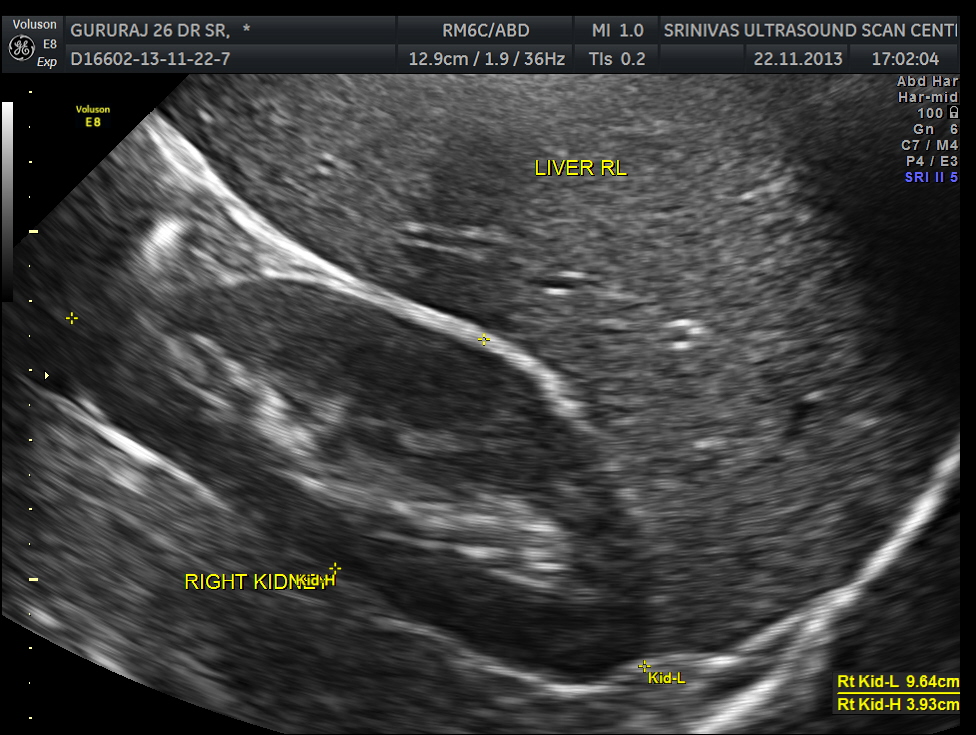

An ultrasound abdomen was done as part of evaluation of anemia.

This was a 27 year old man working as an I.T.consultant in a city. He started getting headaches , which were disabling . The headache was mostly one sided . He was evaluated for the headache ; His CT scan of the brain was normal. He had features of iron defeciency anemia with thrombocytosis . His neurologist after a bit of trial and error made a diagnosis of ‘ indomethacin sensitive chronic paroxysmal hemicranial headache ‘ . He responded very well to indomethacin . But his anemia was not improving with medical treatment.